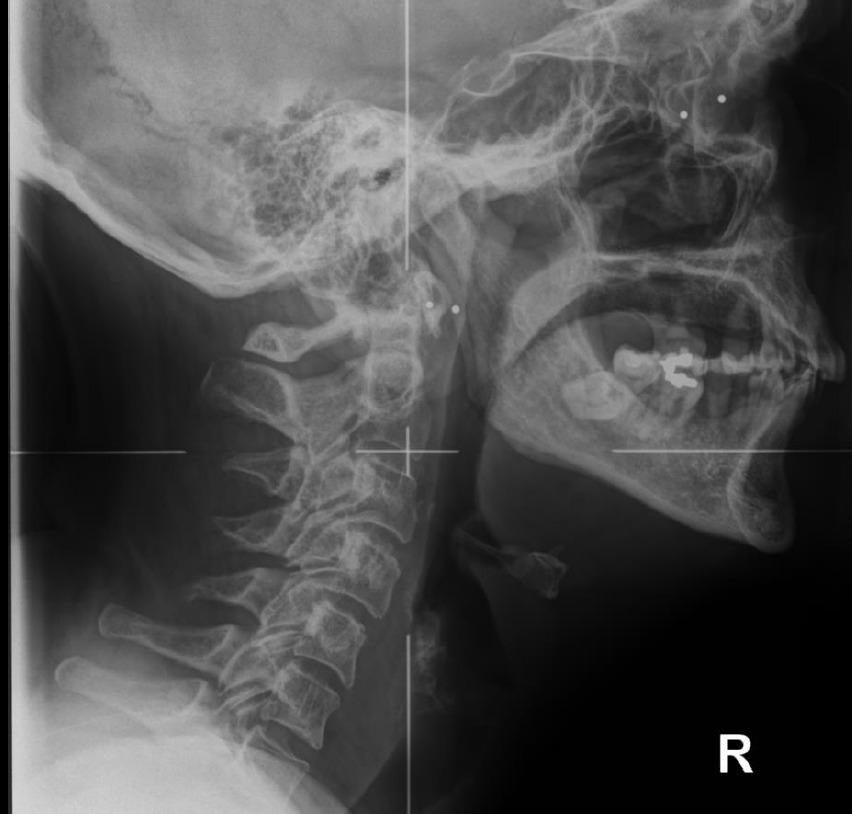

Pictured below is a neutral lateral radiograph (Figure 4) and sagittal slice of a CBCT image of the same patient (Figure 5)

It is important to keep in mind that chiropractors take multiple images of the same anatomic region when using traditional radiographs to obtain the necessary detail needed for proper treatment. As we begin to consider patient dose, the effective patient dose to obtain an image similar to that of Figure 4 (lateral cervical radiograph) is 0.02 mSv (20 μSv) and for an AP cervical spine radiograph is 0.12 mSv.7